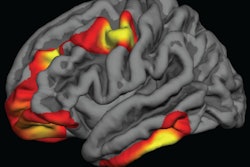

The findings, published online June 14 in PLOS One, target a larger volume of gray matter in the dorsolateral prefrontal cortex of the brain, which is associated with executive functions and working memory.

"We found that the region in the left frontal part of the brain known as left dorsolateral prefrontal cortex was directly related to this discrepancy," Patael said.

Their analyses found that the density of neurons in the dorsolateral prefrontal cortex and its association to executive functions and working memory predated mature reading ability and predicted discrepancies in understanding text, regardless of their initial reading abilities.